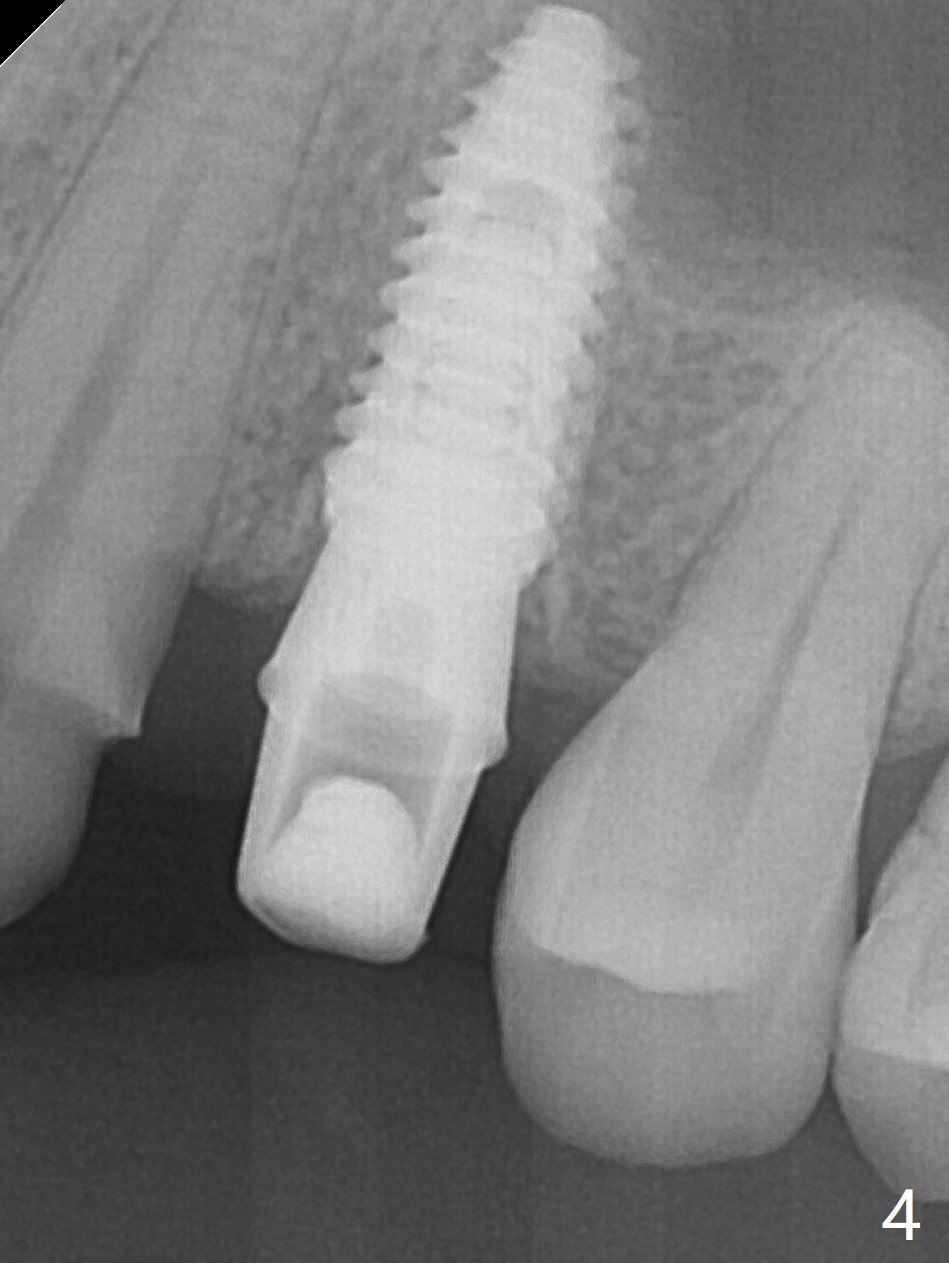

After extraction of the residual roots at #12 and crown prep at #11, osteotomy at #12 is established with Pointed Lindamann bur and 2.2 mm bur for ~ 15 mm. There feels to be sinus floor perforation; a parallel pin is inserted deeper than expected (Fig.1), but there is no membrane perforation. Following sequential osteotomy, a 4x10 mm dummy implant is placed partially with stability (Fig.2). When the same sized definitive implant is placed subcrestally (Fig.3-5 (*: Vera Graft)), the stability remains (~60 Ncm) in spite of the fact that the trajectory is changed once. The coronal socket does not seem to heal 8.5 months postop, in part due to poor hygiene of splinted provisional (Fig.6).